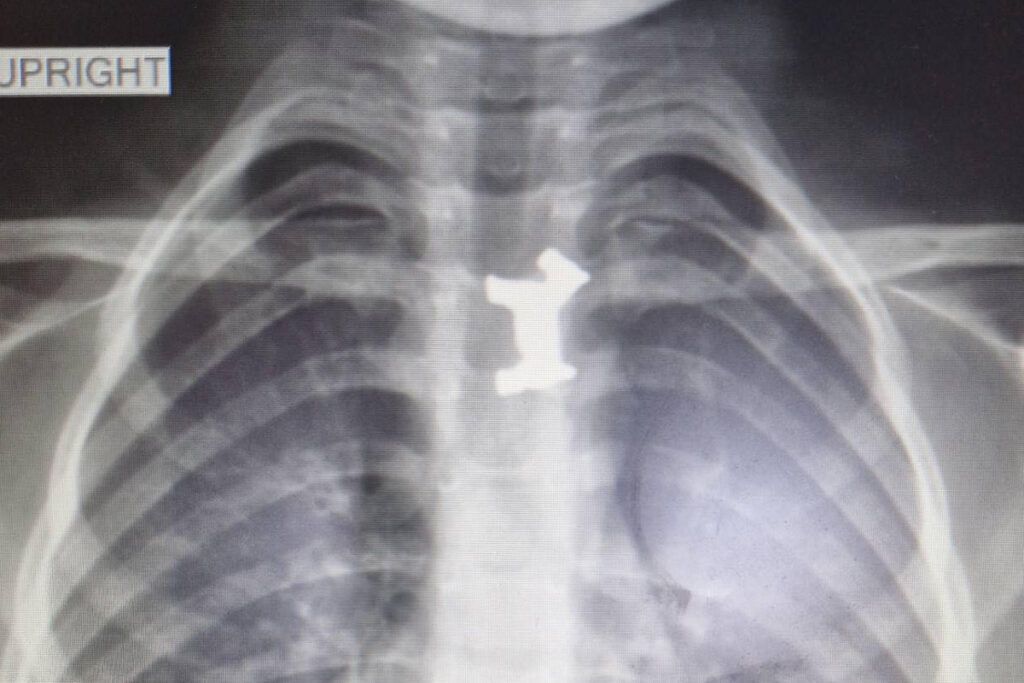

Το αγοράκι εμφάνισε σιελόρροια και οι γονείς του το πήγαν στο Γενικό Νοσοκομείο Σερρών. Εκεί, εξετάστηκε από τους γιατρούς και η ακτινογραφία έδειξε ότι είχε καταπιεί και είχε σφηνώσει στον οισοφάγο του ένα μεταλλικό παιχνίδι. Αποφασίστηκε η διακομιδή του στο Ιπποκράτειο Νοσοκομείο Θεσσαλονίκης.

Η χειρουργική επέμβαση του αγοριού από τις Σέρρες πραγματοποιήθηκε το πρωί της Τρίτης. Οι παιδογαστρεντερολόγοι μαζί με τους παιδοαναισθησιολόγους του Ιπποκρατείου Νοσοκομείου, κατάφεραν να αφαιρέσουν επιτυχώς το μεταλλικό σκυλάκι από τον οισοφάγο του.

Εκεί οι παιδίατροι ακολούθησαν την προβλεπόμενη διαδικασία σε αντίστοιχες περιπτώσεις. Το πρωί υποβλήθηκε σε χειρουργική επέμβαση και οι γιατροί κατάφεραν να αφαιρέσουν με επιτυχία το μεταλλικό σκυλάκι από τον οισοφάγο του παιδιού.